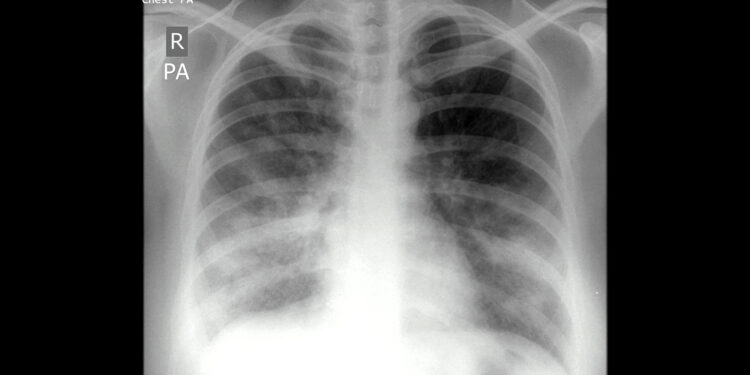

(MedPage Today) — A model that combines a host biomarker with a generative artificial intelligence (AI) analysis of electronic medical records may improve the diagnosis of lower respiratory tract infections (LRTIs), such as pneumonia, in critically…